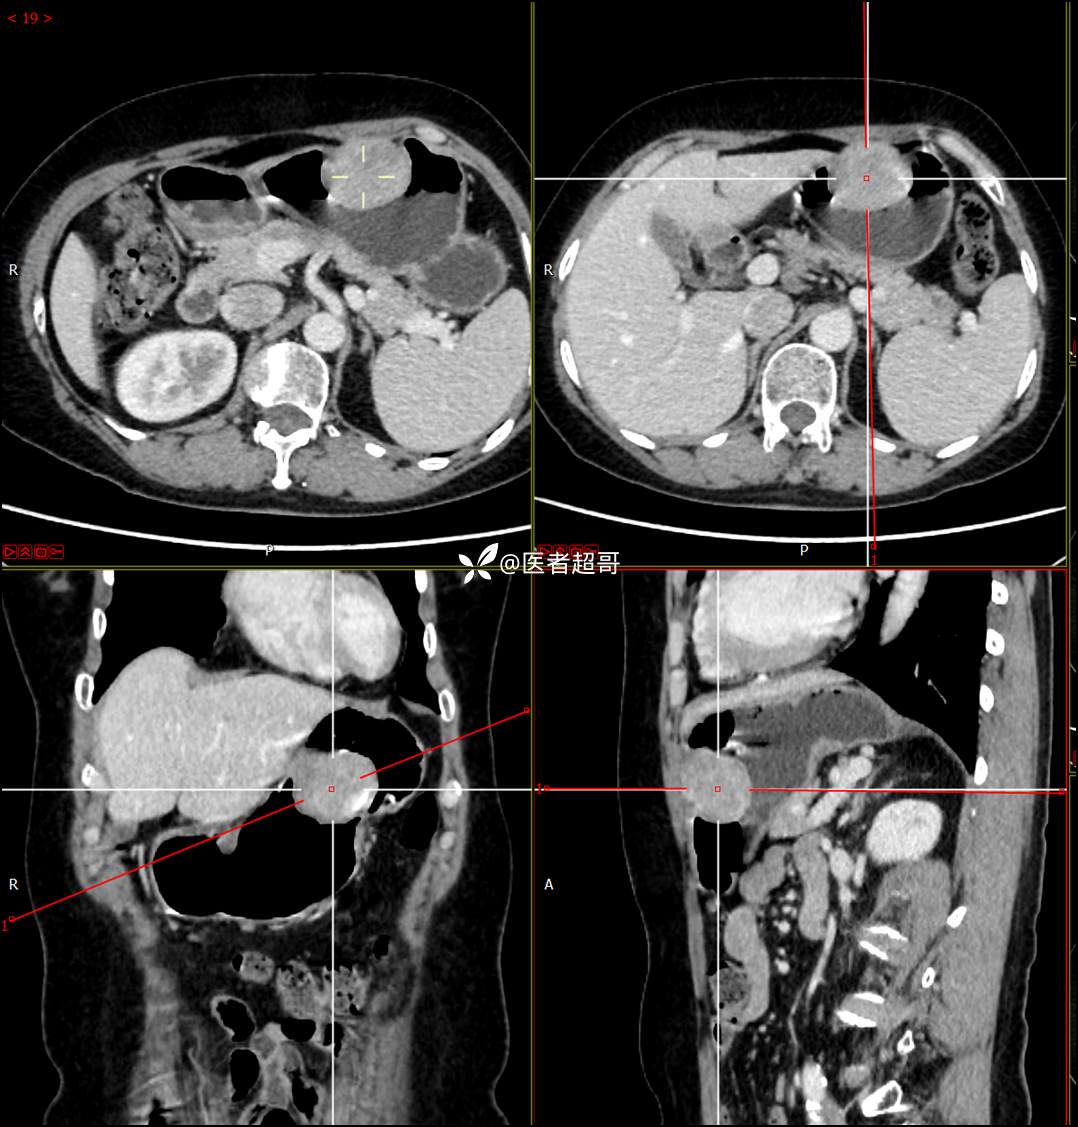

【影诊笔记759】胃体巨大隆起,间质瘤?神经鞘瘤?平滑肌瘤?请鉴别诊断!有结果!

患者半月前无明显原因及诱因出现上腹部疼痛不适,以夜间腹痛为主,无放射性疼痛,间断嗳气,无反酸烧心,无腹泻黑便,于我院门诊行胃镜显示:胃体前壁巨大隆起型病变。